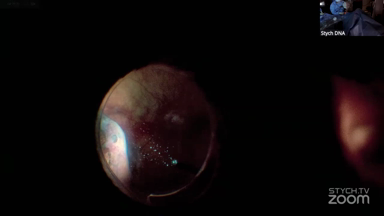

Viewer Discretion Advised: The videos may contain graphic images of surgical procedures that could be disturbing. Viewer discretion is advised. The site is intended for users who are 18 years or older, and no viewers under 18 years of age are allowed unless the use of the site is part of a class within an institution of secondary education and the viewing is supervised by an adult education professional.